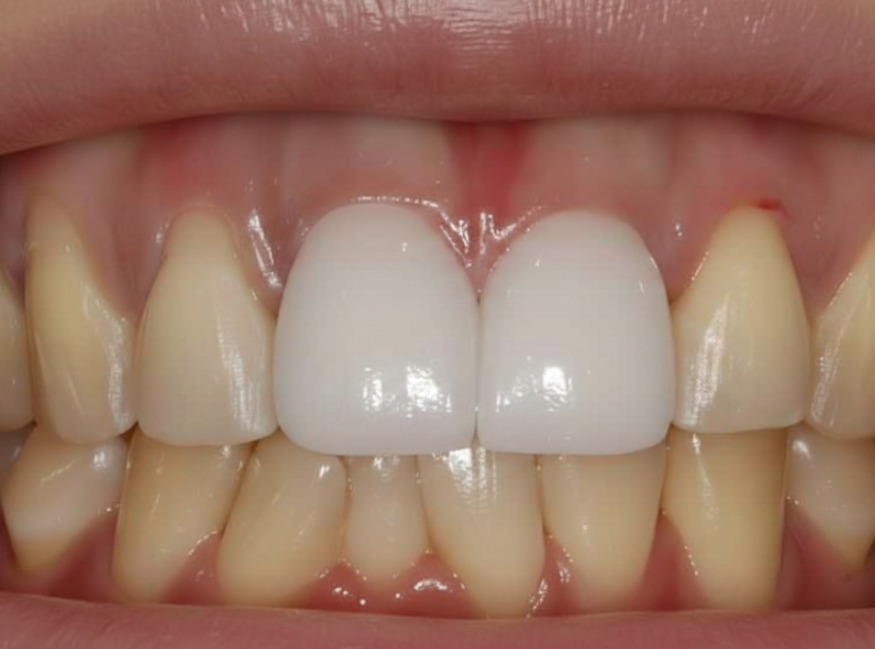

위의 사진처럼 새로 만든 치아가

유독 하얗게 둥둥 떠 보인다면

아무리 튼튼하게 잘 심었어도

성공적인 치료라고 말하기는 어렵겠죠.

주변 치아들과 마치 원래부터 하나였던 것처럼

자연스럽게 어우러지도록 만드는 데

가장 많은 정성을 쏟았습니다.

드디어 완성된 모습입니다.

어떤 게 임플란트인지 한눈에 찾기 어려우시죠?

241101

색상은 물론이고 모양까지

주변 치아와 참 잘 어우러져서

환자분도 저도 무척 만족스러웠던 사례였습니다.^^